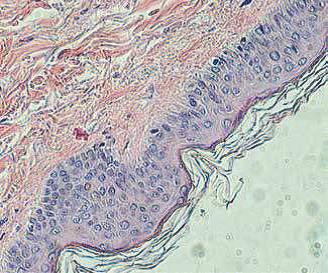

121031100307-3. «Разработка нового способа прогнозирования начала острой реакции трансплантата против хозяина и тяжести ее течения на основании динамики клеточных и гуморальных маркеров». Проведено иммуногистохимическое окрашивание биоптатов кожи у 12 пациентов, выполнен анализ образцов кала методом латеральной иммунохроматографии для определения фекального кальпротектина у 74 пациентов, исследованы уровни фекального зонулина методом иммуноферментного анализа у 75 пациентов. Проанализированы основные таргетные события у исследуемой группы. Продолжено создание банка биообразцов у пациентов после алло-ТГСК, а также биоптатов кожи при развитии клинической картины о.РТПХ с поражением кожи. Проведен анализ плазмы от 84 пациентов после алло-ТГСК в рамках оценки уровней цитокинов (IL-6, sTNFR1) и маркеров клеточного повреждения (ST2, REG3-альфа). При микроскопическом анализе выявлена повышенная экспрессия элафина (более 50 % толщины эпидермиса) в образцах кожи у пациентов с клинической картиной РТПХ кожи. По результатам исследования выявлено статистически значимое повышение уровня кальпротектина и зонулина в кале у группы пациентов с развившейся РТПХ желудочно-кишечного тракта по сравнению с пациентами без РТПХ (р = 0,05). Выявлена повышенная экспрессия элафина в образцах кожи у пациентов с клинической картиной РТПХ кожи. Проводится статистическая обработка результатов анализа уровней цитокинов в плазме.

Полученные результаты позволяют предположить, что фекальный кальпротектин и фекальный зонулин являются диагностическими маркерами развития РТПХ с поражением желудочно-кишечного тракта, а повышенная экспрессия элафина в коже — диагностическим и прогностическим маркером течения острой РТПХ с поражением кожи. Дальнейшее исследование этой темы, расширение размеров когорты позволят подтвердить выявленные закономерности и разработать диагностический протокол, направленный на раннее выявление РТПХ и прогнозирование ее течения.